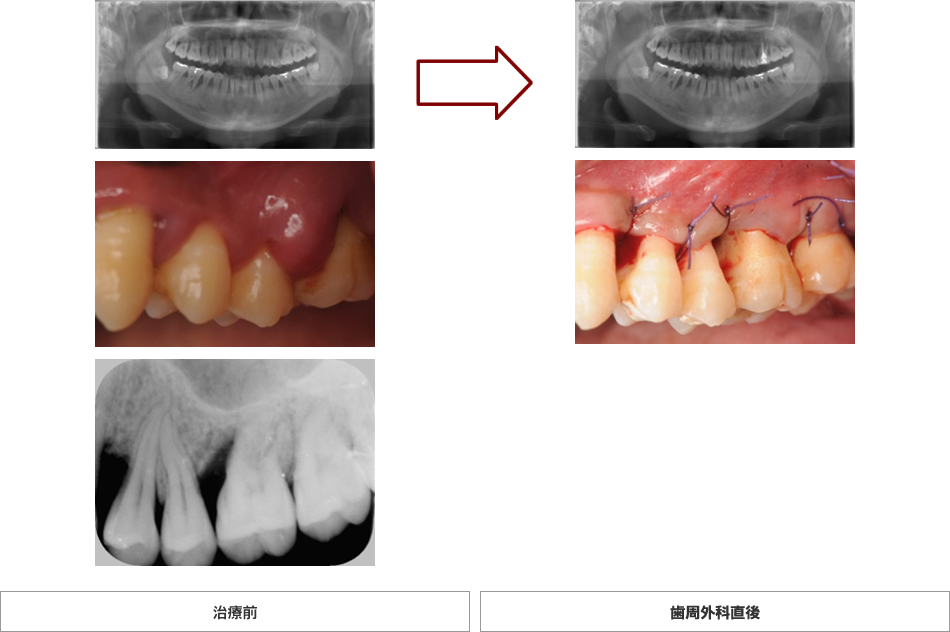

右上臼歯部 歯周外科 H.N様 44歳 女性